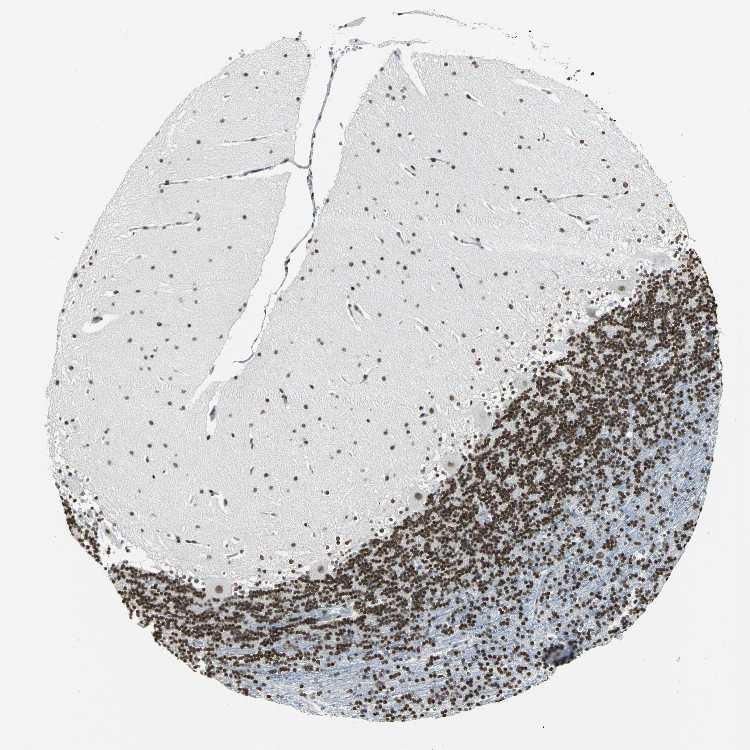

CEREBELLUM - Antibody stainingi

Antibody staining in the annotated cell types in the current human tissue is reported as not detected, low, medium, or high, based on conventional immunohistochemistry profiling in selected tissues. This score is based on the combination of the staining intensity and fraction of stained cells.

Each image is clickable and will lead to virtual microscopy that enables deeper exploration of all samples and also displays staining intensity scores, fraction scores and subcellular localization as well as patient and tissue information for each sample.

Antibody HPA004911

Purkinje cells Medium

Cells in granular layer High

Cells in molecular layer High